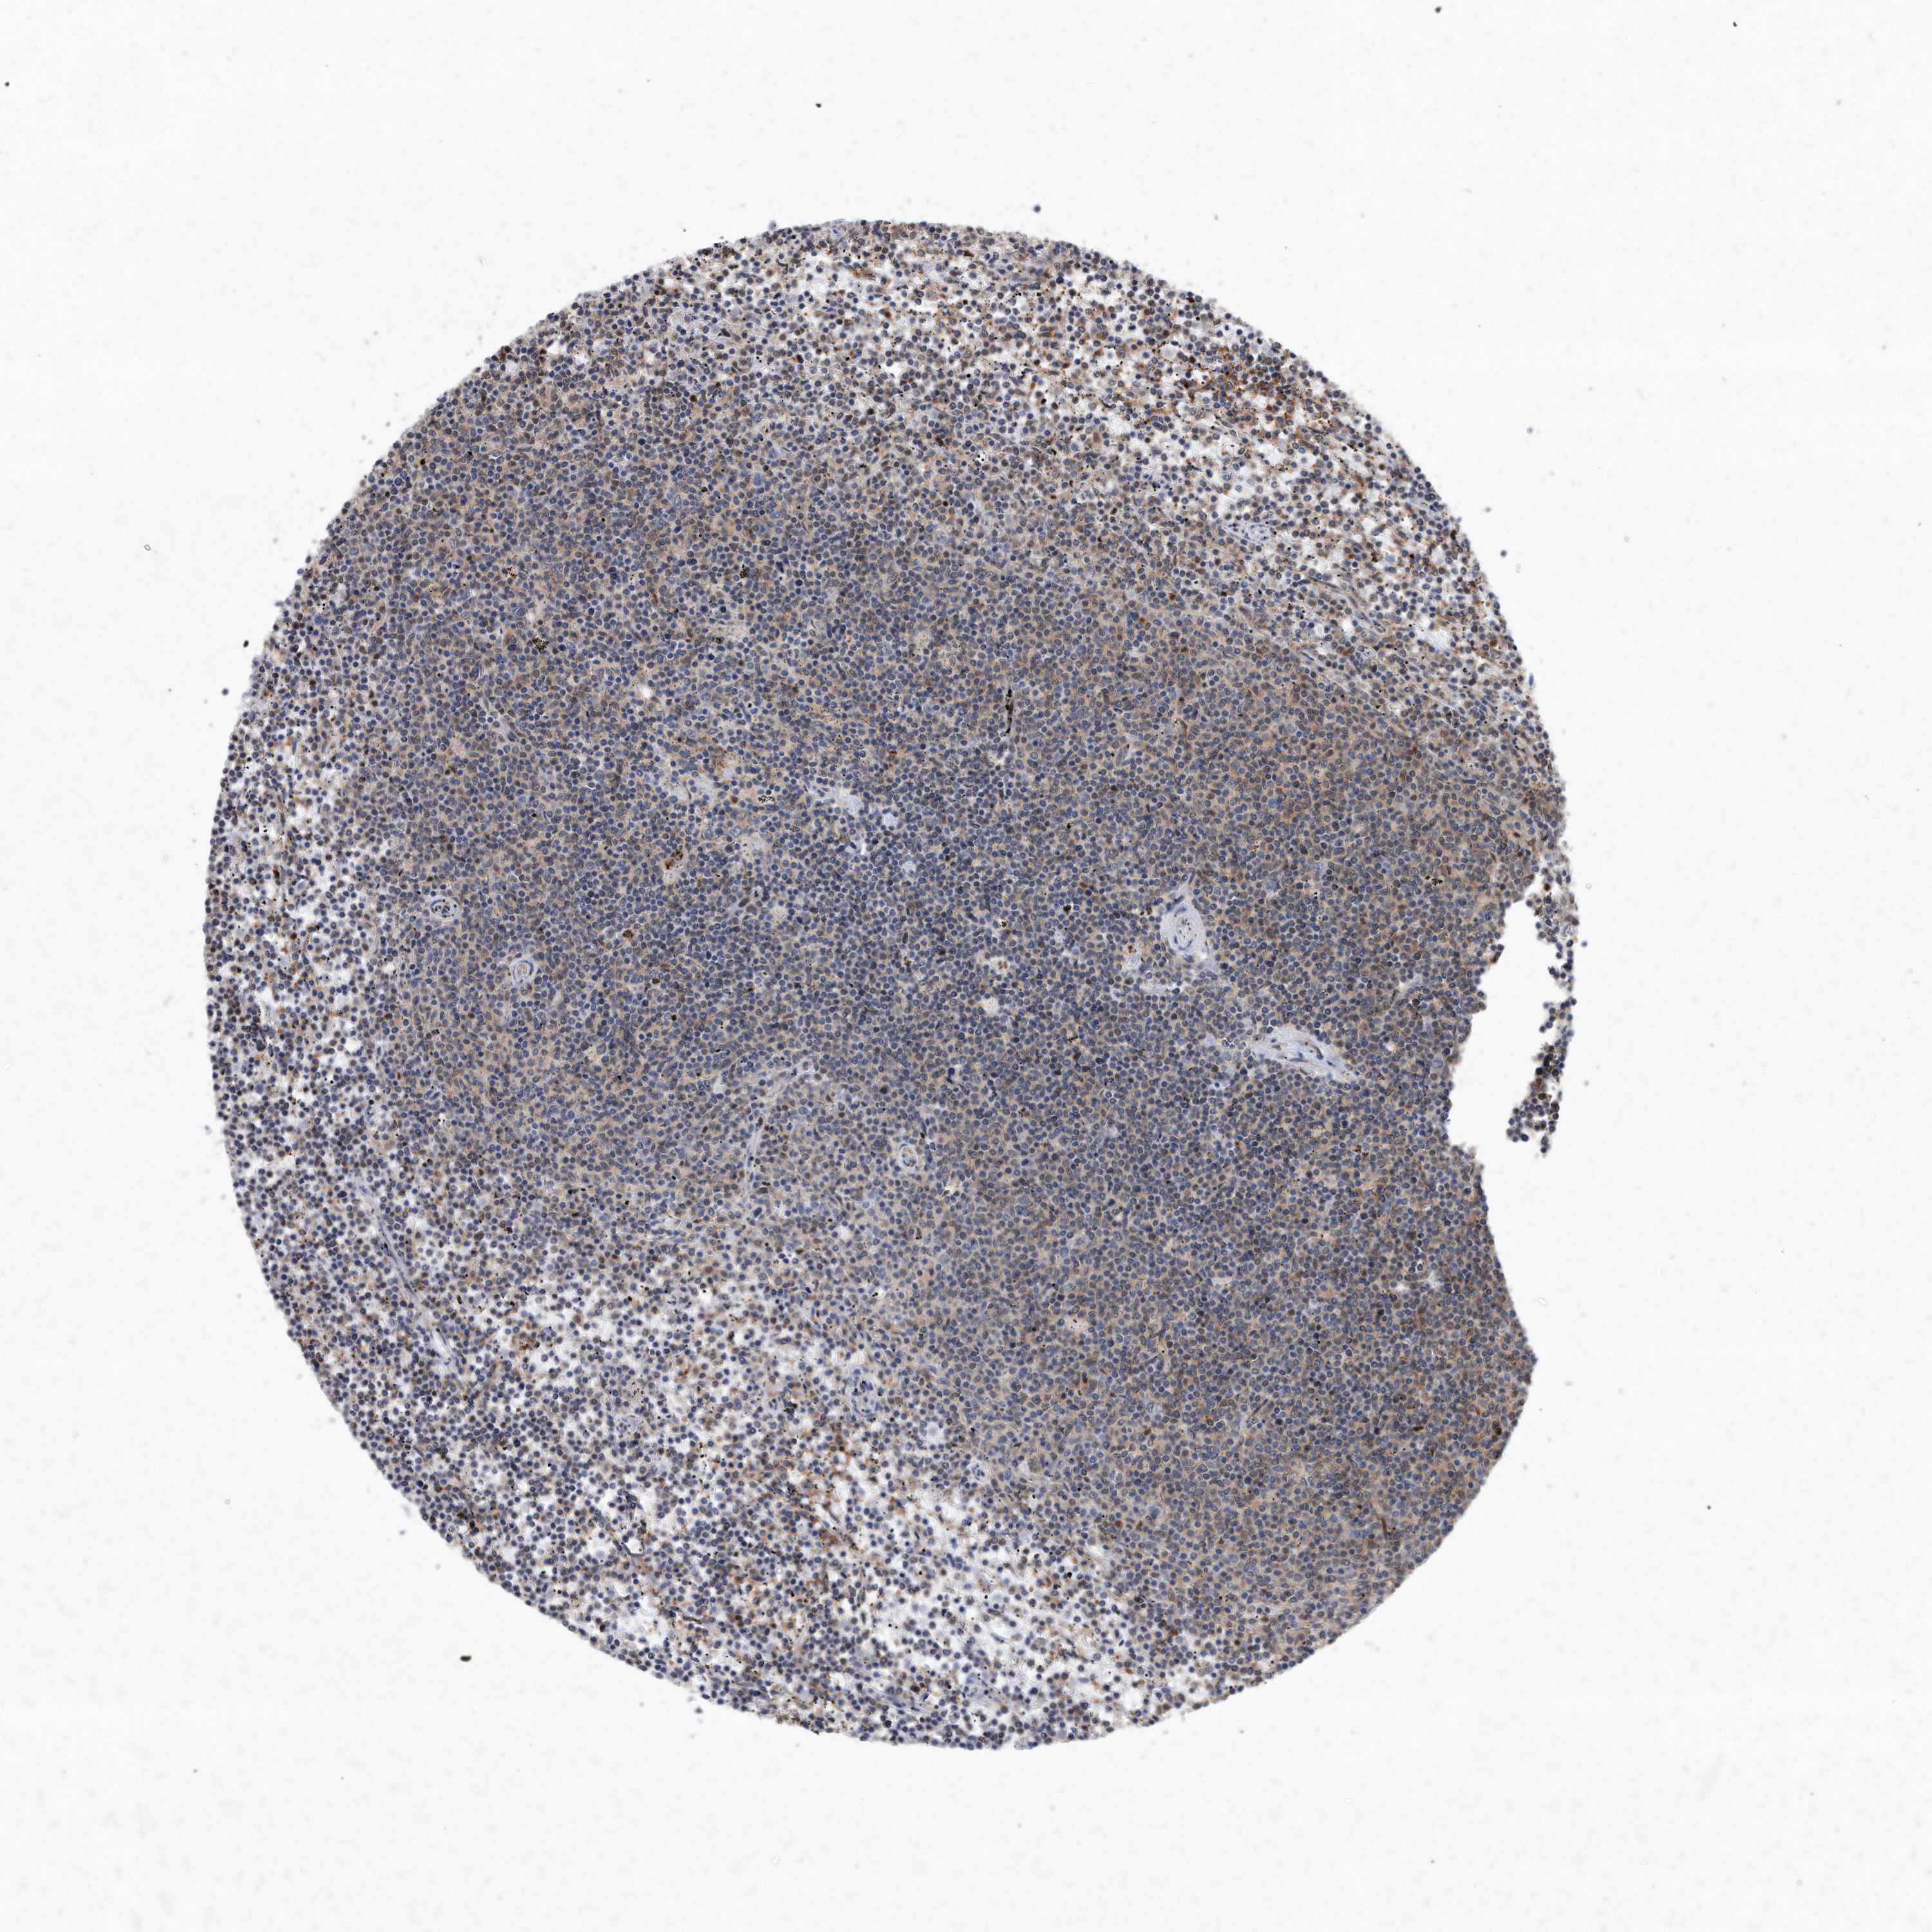

CANCER LYMPHOMA Show tissue menu

LYMPHOMA - Protein expressioni

A mouse-over function shows sample information and annotation data. Click on an image to view it in a full screen mode. Samples can be filtered based on level of antibody staining by selecting one or several of the following categories: high, medium, low and not detected. The assay and annotation is described here.

Each image is clickable and will lead to virtual microscopy that enables deeper exploration of all samples and also displays staining intensity scores, fraction scores and subcellular localization as well as patient and tissue information for each sample.

Antibody HPA029888

Antibody HPA029889

Antibody HPA029890

Hodgkin's disease, NOS

Malignant lymphoma, non-Hodgkin's type, High grade

Malignant lymphoma, non-Hodgkin's type, Low grade